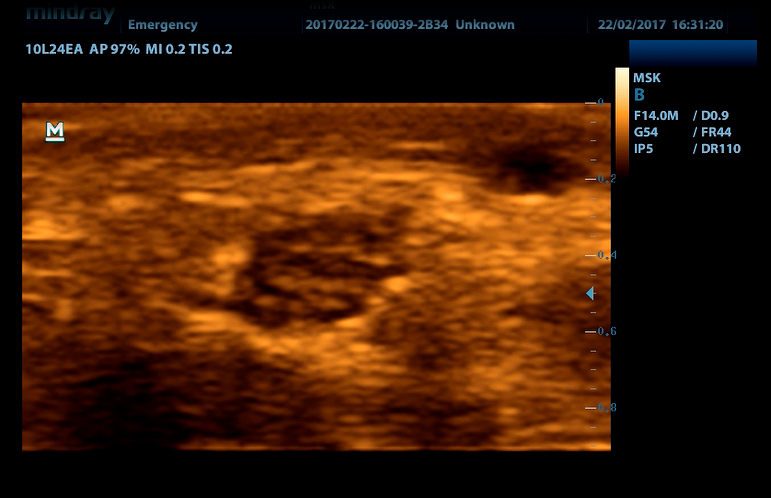

Линейный датчик высокочастотный 10L24EA (8.0/10.0/12.0/14.0/Н10.0/Н12.0 МГц, 24 мм)